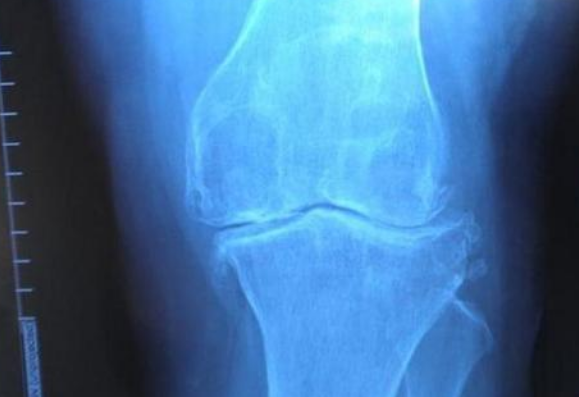

既然早已经被淘汰就说明这个器官作用不大,不至于影响我们日常生活。而这个重新出现的器官叫法贝骨,它属于骨质骨,是在我们膝盖骨上的肌腱中长出来的肌肉。在一些灵猴身上还存在着这种器官,但我们人类很早之前就已经把这个器官淘汰掉了。在19世纪,科学家们发现法贝骨开始重新出现,拥有这个器官的人占到了全球几乎一半的人口。

而法贝骨当年消失可能是因为我们运动量减少,并且营养跟不上,所以这个器官逐渐被我们淘汰。如今它重现,说明我们营养成分和运动量都已经足够。而这个器官其实对我们也有益处,它可以强化我们关节,或许它的重现对我们而言不是退化了。但是这始终还是我们自己猜测,并没有得到科学家们验证。那么你们怎么看法贝骨重现一事呢?